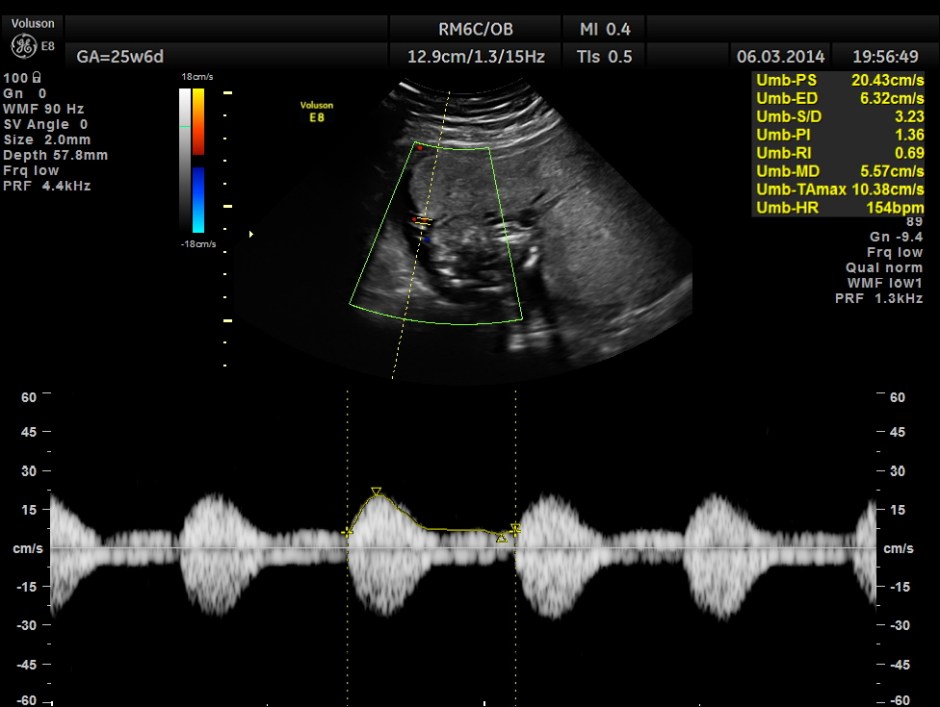

Umbilical arterial P.I. and R.I. are higher for the GA.

Cord with only two vessels seen and umbilical cord measured 20 cms in length.